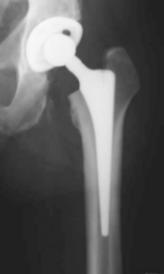

Bei den totalen Hüftendoprothesen (Hüft-TEP) werden in der Regel eine künstliche Hüftpfanne und eine Schaftprothese mit Aufsteckkopf implantiert. Hierfür stehen unterschiedliche Prothesenmodelle und Verankerungsmöglichkeiten (zementiert, zementfrei) zur Verfügung. Eine neuere operative Versorgungsmöglichkeit stellt der Hüftoberflächenersatz dar. Es handelt sich hierbei um ein besonders knochensparendes Prothesensystem, dessen klinischer Einsatz jedoch noch jung ist, sodaß potentielle Vorteile noch nicht abschließend beurteilt werden können.

Bei der zementierten Hüftprothese wird eine anatomisch angepasste Schaftprothese aus einer hochwertigen Edelstahllegierung (CoNi) über Knochenzement in der Markhöhle des Oberschenkelknochens verankert. Der Gelenkpartner zur künstlichen Hüftpfanne besteht in der Regel aus einem Keramikaufsteckkopf.

Bei der zementfreien Hüftprothese besteht die Schaftprothese aus einer speziellen Titanschmiedelegieung, welche das Anwachsen von Knochen fördert. Den Gelenkpartner zur künstlichen Hüftpfanne bildet ein Aufsteckkopf aus Keramik.

Im Vincentiuskrankenhaus werden seit dem Jahr 2002 mit Hilfe von einem speziell entwickelten Instrumentarium minimalinvasive Implantationen von Hüftprothesen durchgeführt. Hierdurch gelingt es die Länge der sichtbaren Operationsnarbe deutlich unter 10cm zu halten, wenn keine Fettleibigkeit beim Patienten vorliegt. Durch die minimalinvasive Technik wird das Gewebe geschont und der Blutverlust verringert. Es besteht die Tendenz zur schnelleren Rehabilitation.